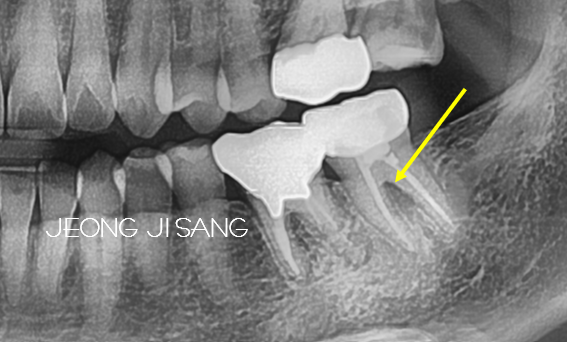

엑스레이를 촬영합니다.

엑스레이를 보면 치아 뿌리 중간 쪽으로 뭔가 심상치 않습니다.

바로 여기입니다.

앞에 있는 뿌리 쪽으로 얇아져있고 해당부위에 골소실양상을 보이고 있습니다.